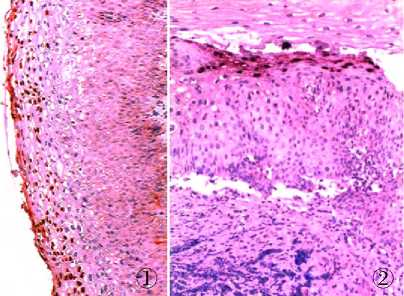

两组CIN2标本病例数如下:A组75例,B组58例。 HPV L1壳蛋白为壳蛋白质,阳性部位在细胞核,胞核呈红色为特异性阳性染色,其它部位的红染均为非特异性染色。镜下见明确被红染的细胞核即可诊断为HPVL1阳性。采用环保型GS组织样本制备套液制作的标本能检测组织中相应抗原,定位准确,背景清晰;经GS环保试剂处理的标本染色效果与传统方法相同(图1、2)。两组标本中HPVL1阳性率,差异无统计学意义(P =0.81,表1)。

图1传统脱水剂:HPV Ll壳蛋白原位杂交检测效果

图2环保试剂脱水:HPV Ll壳蛋白原位杂交检测效果